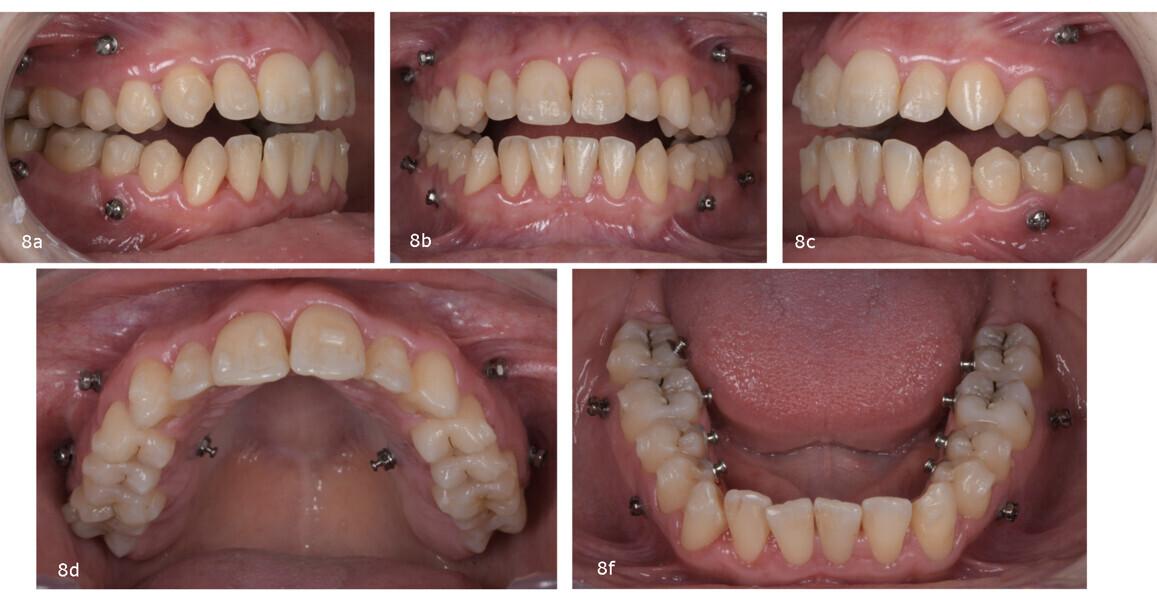

At the initial appointment, the attachments were bonded. In the maxilla, mini-screws (1.6 × 10.0 mm) were placed buccally between the first and second premolars and between the first and second molars, and palatally between the first and second premolars. The patient was instructed to wear 5/16 in., 8 oz vertical elastics bilaterally extending from the buccal to the palatal mini-screws over the aligners. In the mandibular arch, mini-screws were inserted buccally between the first and second premolars and between the first and second molars. The patient was instructed to wear elastics from these mini-screws over the aligners to lingually bonded buttons (Fig. 8).

After the 20th aligner, we initiated the reset phase, pausing treatment to rescan the patient and replan the final phase. At this stage, crowding had been resolved, and the open bite had been closed, although additional posterior intrusion was still needed to establish a stable correct overbite. This mid-treatment refinement is crucial to ensure precise fit and continued accuracy of the aligners.